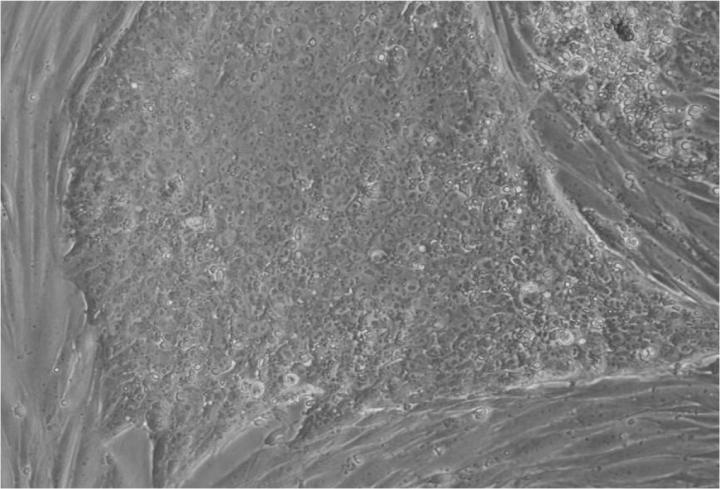

人類(lèi)胚胎干細(xì)胞 (ESC) 是從囊胚(一種非常早期的人類(lèi)胚胎)中發(fā)現(xiàn)的少量細(xì)胞產(chǎn)生的。從囊胚中取出的單個(gè)細(xì)胞生長(zhǎng)成大量細(xì)胞以產(chǎn)生 ESC“系”。

胚胎干細(xì)胞的自我復(fù)制能力允許從干細(xì)胞系中培養(yǎng)出大量細(xì)胞,并與全球?qū)嶒?yàn)室共享多年,從而最大限度地減少了從囊胚制造新胚胎干細(xì)胞的需求。

Jenny Nichols 拍攝的人類(lèi)囊胚和人類(lèi)胚胎干細(xì)胞圖像。愛(ài)丁堡大學(xué) MRC 再生醫(yī)學(xué)中心向 SCNT 和多莉羊注射細(xì)胞核。